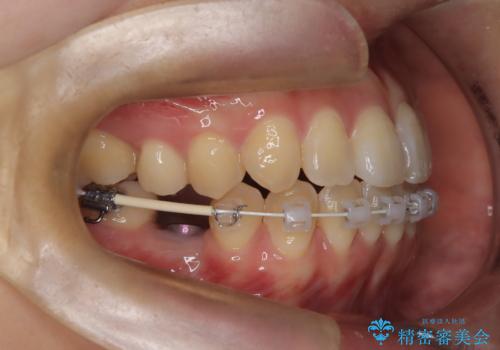

- 矯正装置

- 審美装置

- 治療期間

- 1年6ヶ月

また、欠損部にインプラントを埋入するには、前後の歯の傾斜改善とスペース確保のための矯正治療が必要でした。

下顎前歯の叢生も同時に改善できるよう、全体的なワイヤー矯正による治療計画を立案しました。